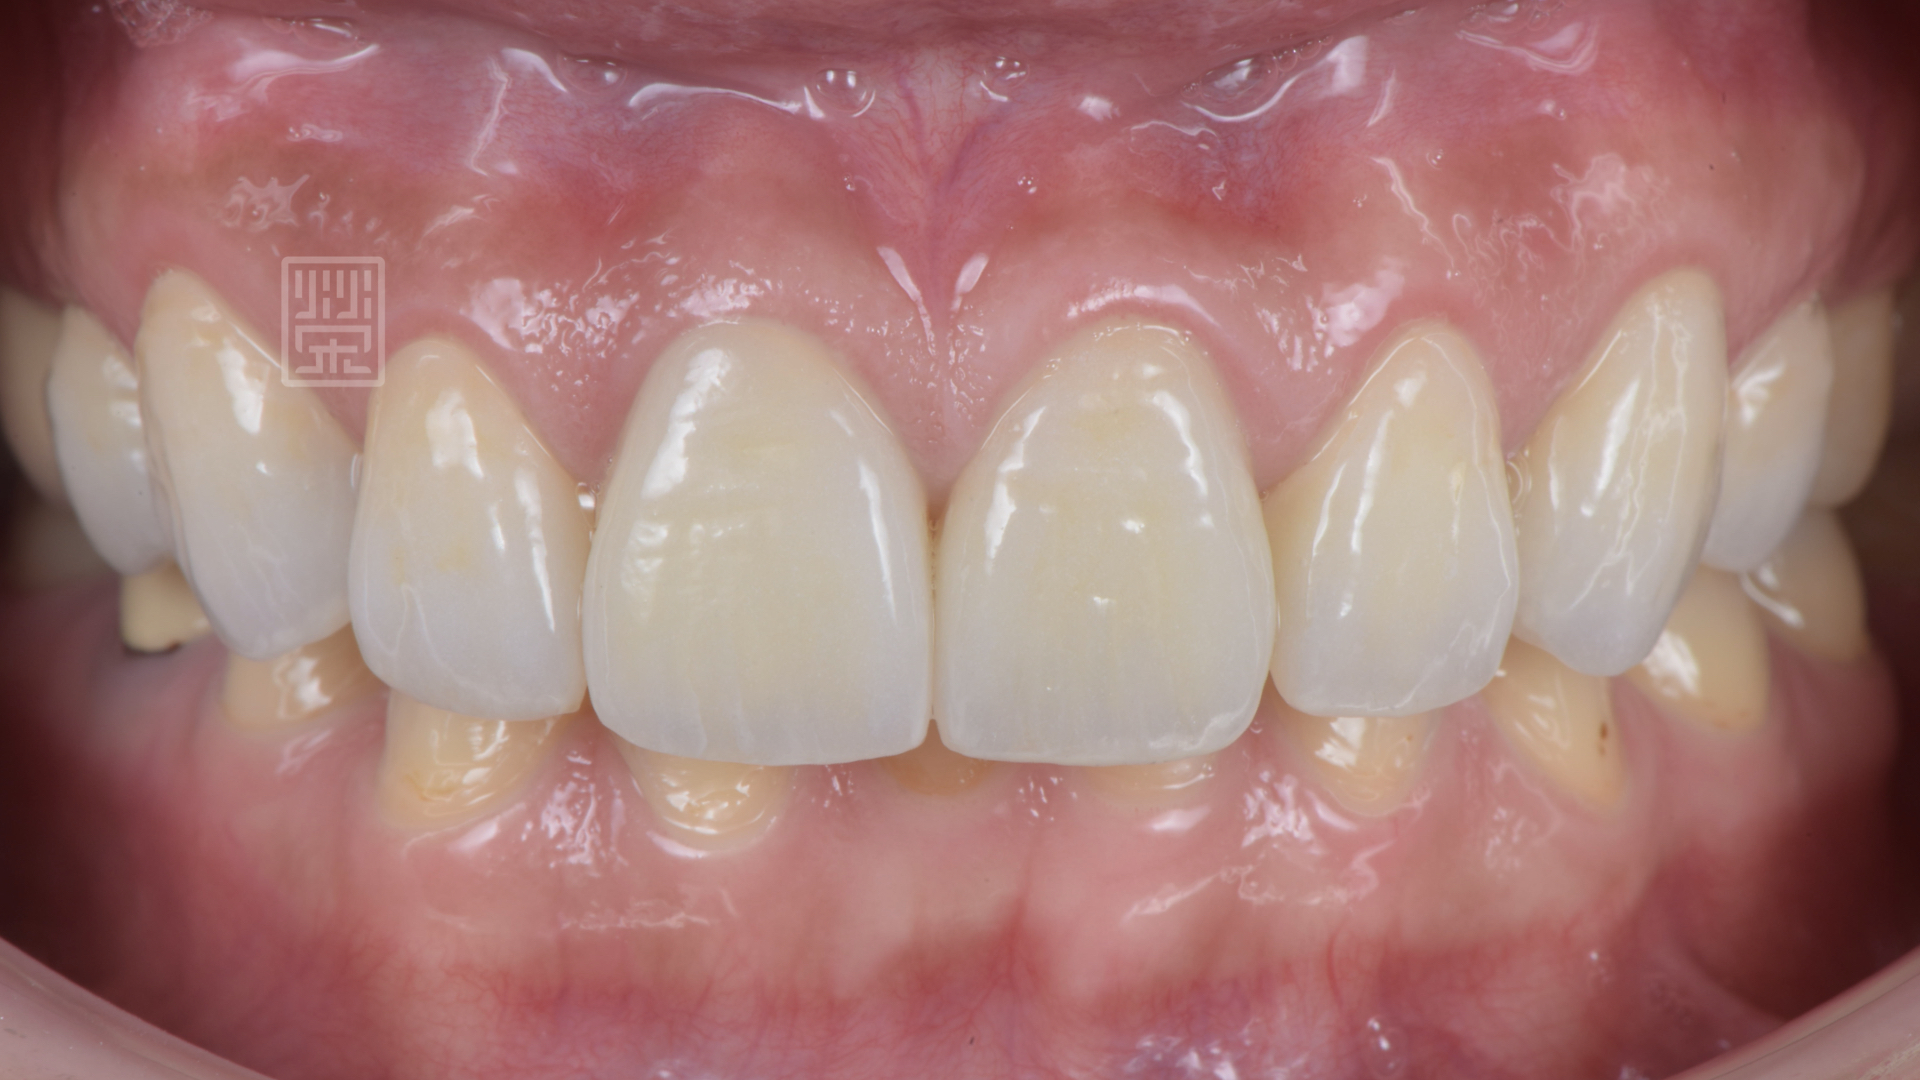

等到植體癒合穩定後,針對牙齒的長度為製作模擬溝通,顏色部分希望自然白亮即可,所以選擇自然齒色中最白亮的色階,讓整體笑容更加和諧。

植牙、全瓷冠、全瓷貼片完成

貼片全瓷冠與笑容和諧